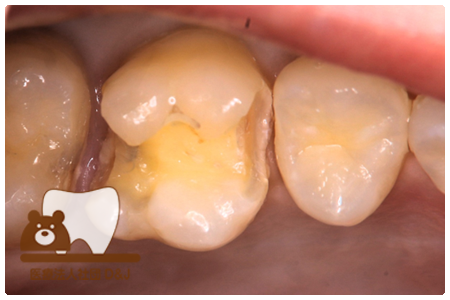

症例8フルジルコニアクラウン

治療前

治療中

治療後

29歳 女性

- 治療内容

- 銀歯からフルジルコニアクラウンへの修復

- 治療期間

- 根の治療含め3か月

- 費用

- 自費

フルジルコニアクラウン:77,000円(税込)

- その他の治療の費用は含まれておりません。

- リスク・副作用

- 強い衝撃が加わると欠けたり割れたりする可能性があります。また、噛み合わせの状態によっては脱離や周囲の歯への影響が出ることもあります。